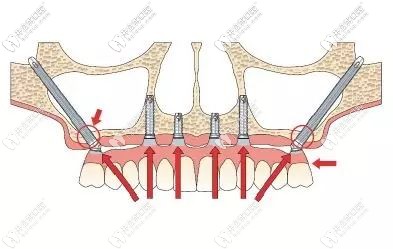

穿顴骨種植技術(shù),也被稱為“無土栽培”技術(shù)。杭州美奧口腔王明來給大家詳細(xì)講解什么是穿顴種植,以及穿顴骨種植的利弊有哪些。